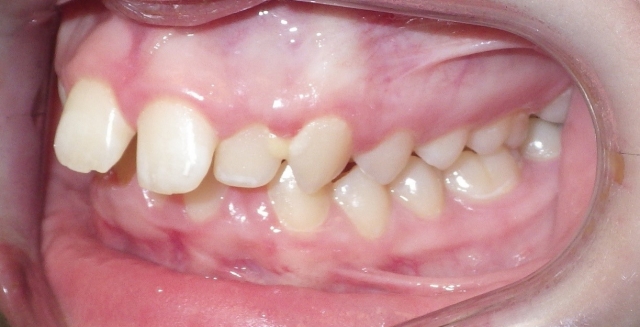

Monitoring the erupting dentition can help the patient receive the correct timing for intervention. A panoramic image as a screening procedure can confirm if there is adequate space for full permanent tooth eruption, if the eruption sequence is normal and if there are any impediments to eruption present. In Class II growth patterns in particular, noting the time for eruption of the upper second molar can make a difference in the ease of establishing the Class I molar relationship. Using methods to increase the arch length by distalizing the upper first molar can provide the dual benefit for adequate eruption space and the molar correction. (Fig. 2 and 3)

The arch form is also an important factor to evaluate in a Class II pattern. If the upper arch form is narrow, the upper incisors are more protrusive with an increased overjet. (Fig. 5 and 6) The maxilla appears “V” shaped from the occlusal view. (Fig. 7 and 8) The lower arch form is often broader because it is set more posterior in a wider area of the upper arch. If the full upper arch form is not expanded, there will be an excess overjet that remains. Imagine trying to align a round circle into the peak of a triangle. If the full arch is expanded with an expander, the upper and lower arches can coordinate to a normal overjet. (Fig. 4)